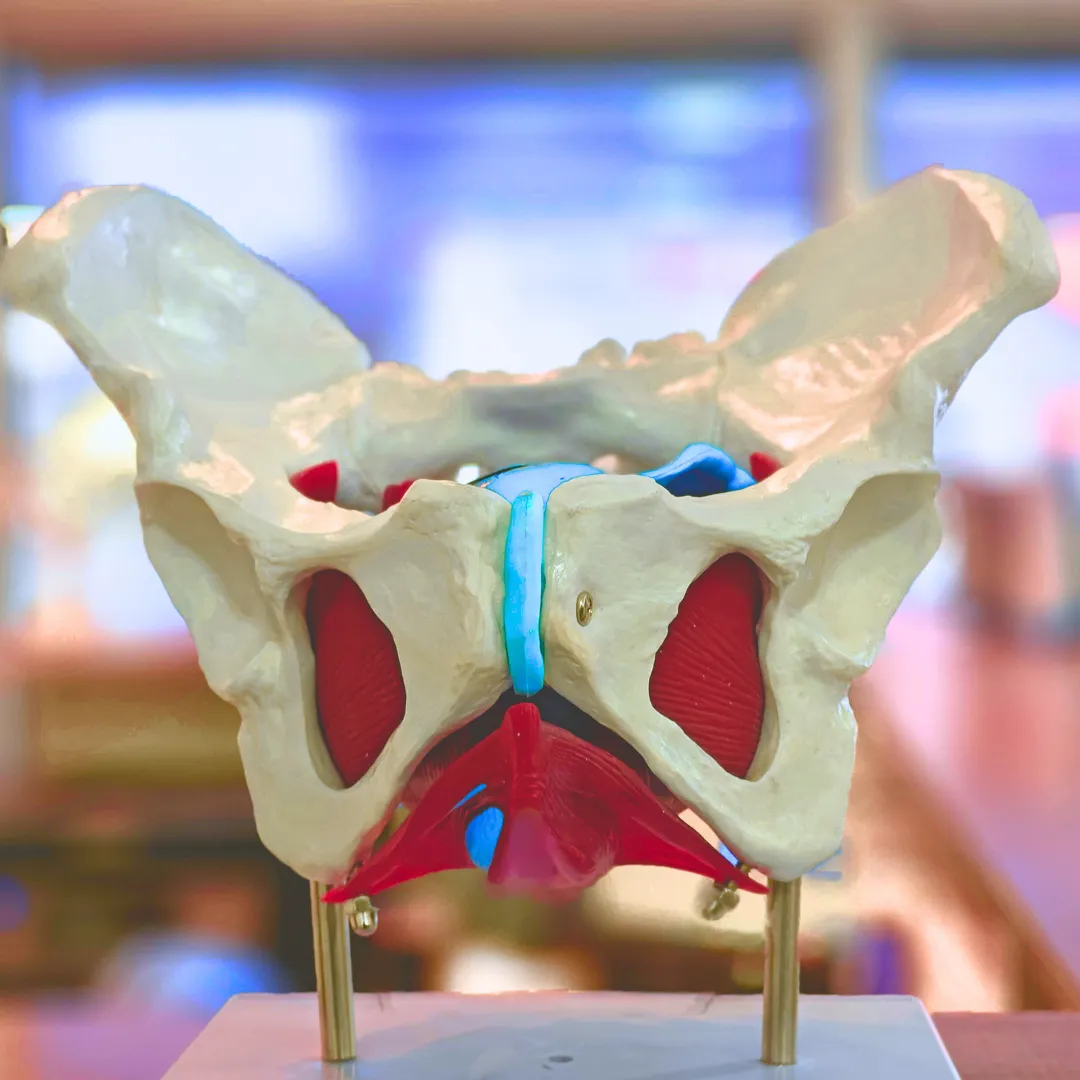

FISIOTERAPIA DE

PISO PÉLVICO

Mujeres

Incontinencia urinaria

Prolapsos

Dolores en las relaciones sexuales

Hombres

Problemas de erección

Problemas de próstata

Eyaculación precoz